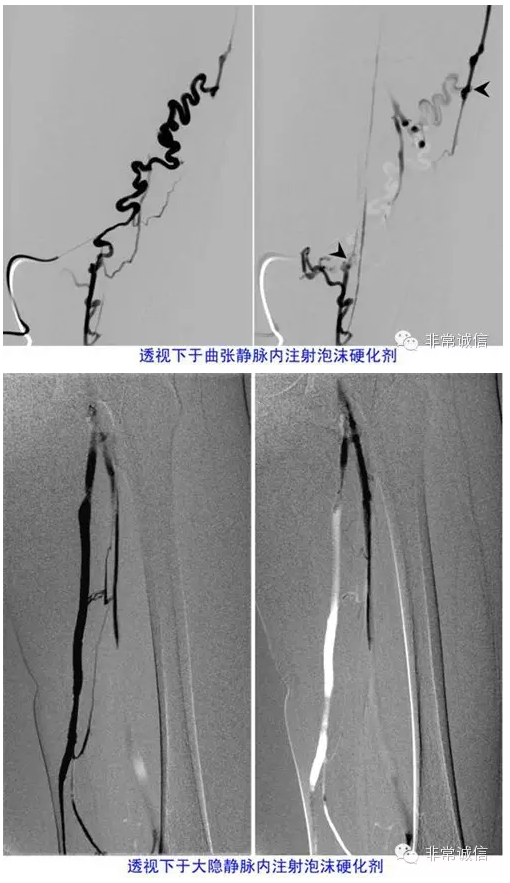

最新疗法-----透视引导下泡沫硬化疗法

在注射泡沫硬化剂前先注入碘对比剂使静脉显影,在X线监控下注射入血管内的以气体为主要成分的泡沫硬化剂在高密度的碘对比剂衬托下显示为低密度的充盈缺损;当曲张静脉内的对比剂完全被泡沫置换(曲张静脉充满泡沫硬化剂)和(或)见泡沫硬化剂即将进入深静脉时停止注射泡沫硬化剂。X线透视引导下的泡沫硬化剂注射过程可称之为X线透视引导下的充盈缺损技术,患者的辐射剂量是可能接受的。